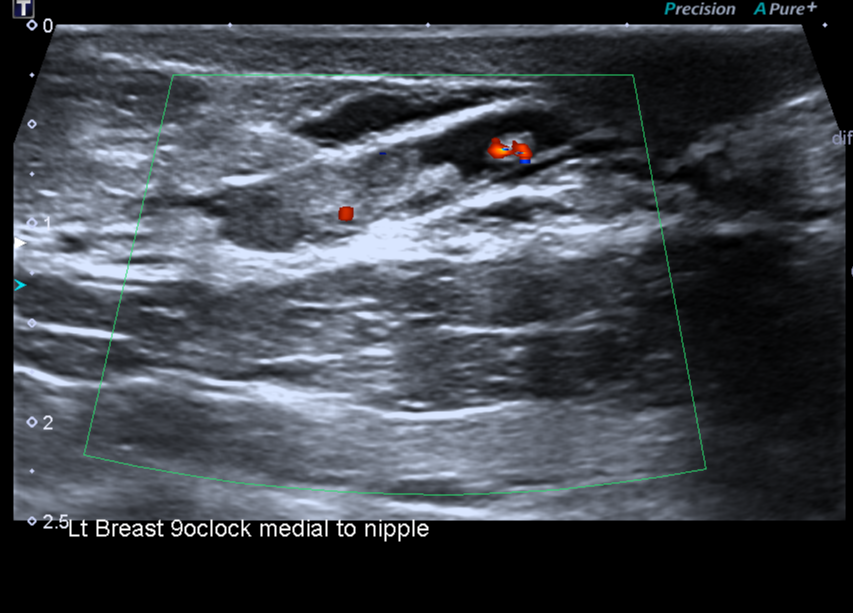

Intraductal papilloma on ultrasound image

Intraductal papilloma on ultrasound image. Author: Bruno Di Muzio. Source: Radiopaedia [11]

2. Breast ultrasound and peripheral lymph nodes: a mass protruding into the lumen of the duct or cystic cavity is visualized.